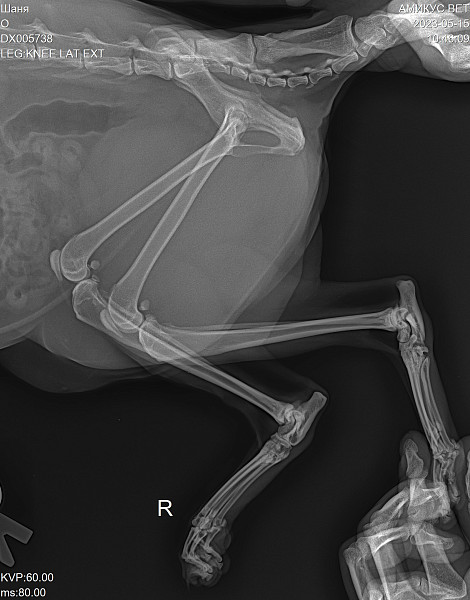

Рентгенологическая диагностика саркомы у кошек

Раздел: Визуальный дайджест